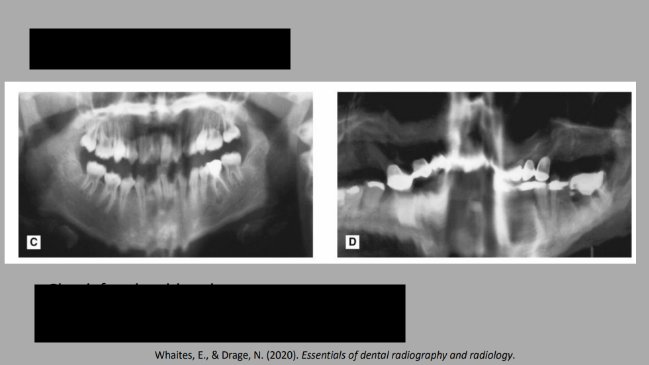

Errors in patient preparation

Image 1: Ghost image of a necklace/chain. Also jaw surgery.

Image 2: Lead apron